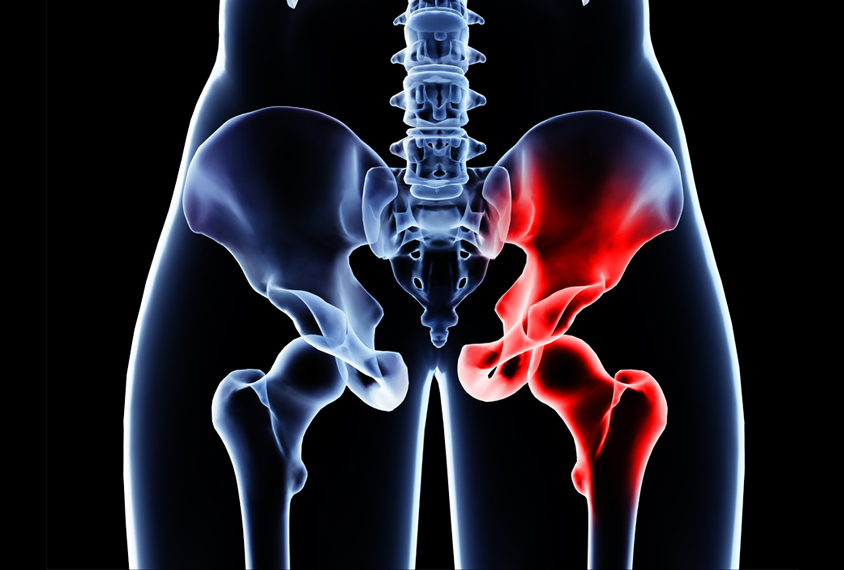

고관절 통증 증상(엉덩관절)은 오른쪽과 왼쪽의 골반과 넙다리뼈가 연결된 관절의 통증을 일컫습니다. 고관절은 상체의 하중을 분산시키는 역할을 하며, 일어서거나 앉거나 일상생활에서 자주 쓰이는 관절이며 부담도 잘 받게 됩니다. 모양도 크기도 탁구공만 합니다. 일상적으로 걸을 때 고관절에 체중의 3~4.5배의 무게가 실리게 됩니다. 계단을 오를 때는 대퇴골두에 전해지는 무게는 몸무게의 8배, 달리는 경우 10배에 가까운 하중을 견뎌내애 한다고 합니다. 탁구공 크기만 한 대퇴골두가 감당하기에는 너무 무겁기 때문에 고관절이 느끼는 부담도 크고 쉽게 손상될 수 있습니다. 다른 관절과 마찬가지로 감당하기 어려운 충격이나 무게가 가해지면 고관절 통증 증상이 발생하게 되는데요. 퇴행성 고관절염, 대퇴골 골절, 대퇴골두 무혈성 괴사, 선천성 고관절 탈구 등이 대표적인 고관절 통증 질환입니다.